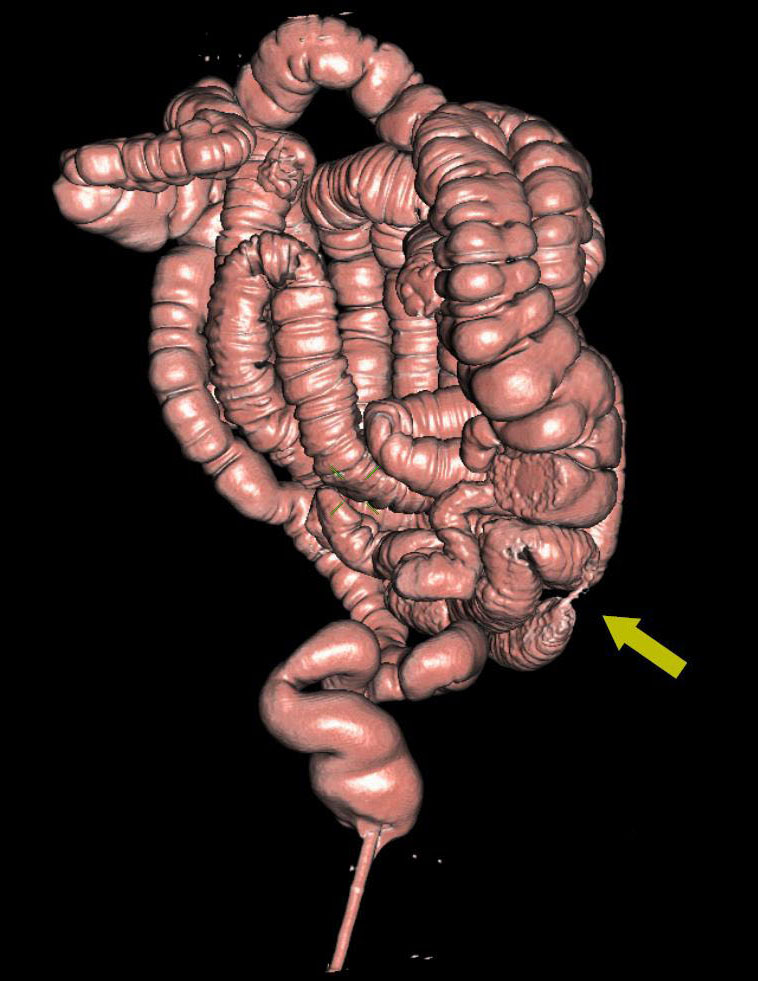

Рак ободочной кишки в зоне селезёночного угла с прорастанием опухоли в переднюю стенку желудка

Патология с точки зрения диагностики так и клиники интересна тем, что диагностировать удалось в полном объёме только на КТ, при проведении виртуальной колоноскопии. 3D реконструкция и в этом случае, как нельзя кстати. Пациент удачно прооперирован, с восстановлением физиологии пищеварительной трубки с относительно благоприятным клиническим исходом. Через год после комбинированного лечения отдалённых метастазов не выявлено.